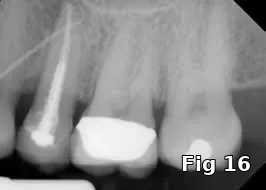

Ridge preservation — use as a membrane: Here is a 40-year-old male who presented for the evaluation of a painful swelling in his gum (Fig. 15). Diagnosis was peri-apical abscess with sinus fistula, possible midroot fracture of tooth #13 (Fig. 16) and a treatment plan to extract the tooth (Fig. 17) and ridge preserve followed by implant placement and an implant-supported fixed restoration.

Here PRGF graft was helpful in securing the buccal fenestration defect at the apex prior to bone grafting (Fig. 18) allowing for secure placement and containment of the bone graft (Fig. 19) and PRGF membrane (Fig. 20) for ridge preservation. Flaps were readapted and closed over the PRGF membrane (Fig. 21) and one-week postoperative shows complete closure of the soft tissue over the extraction socket (Fig. 22) and complete resolution of the sinus tract and swelling in the buccal gingival (Fig. 23).